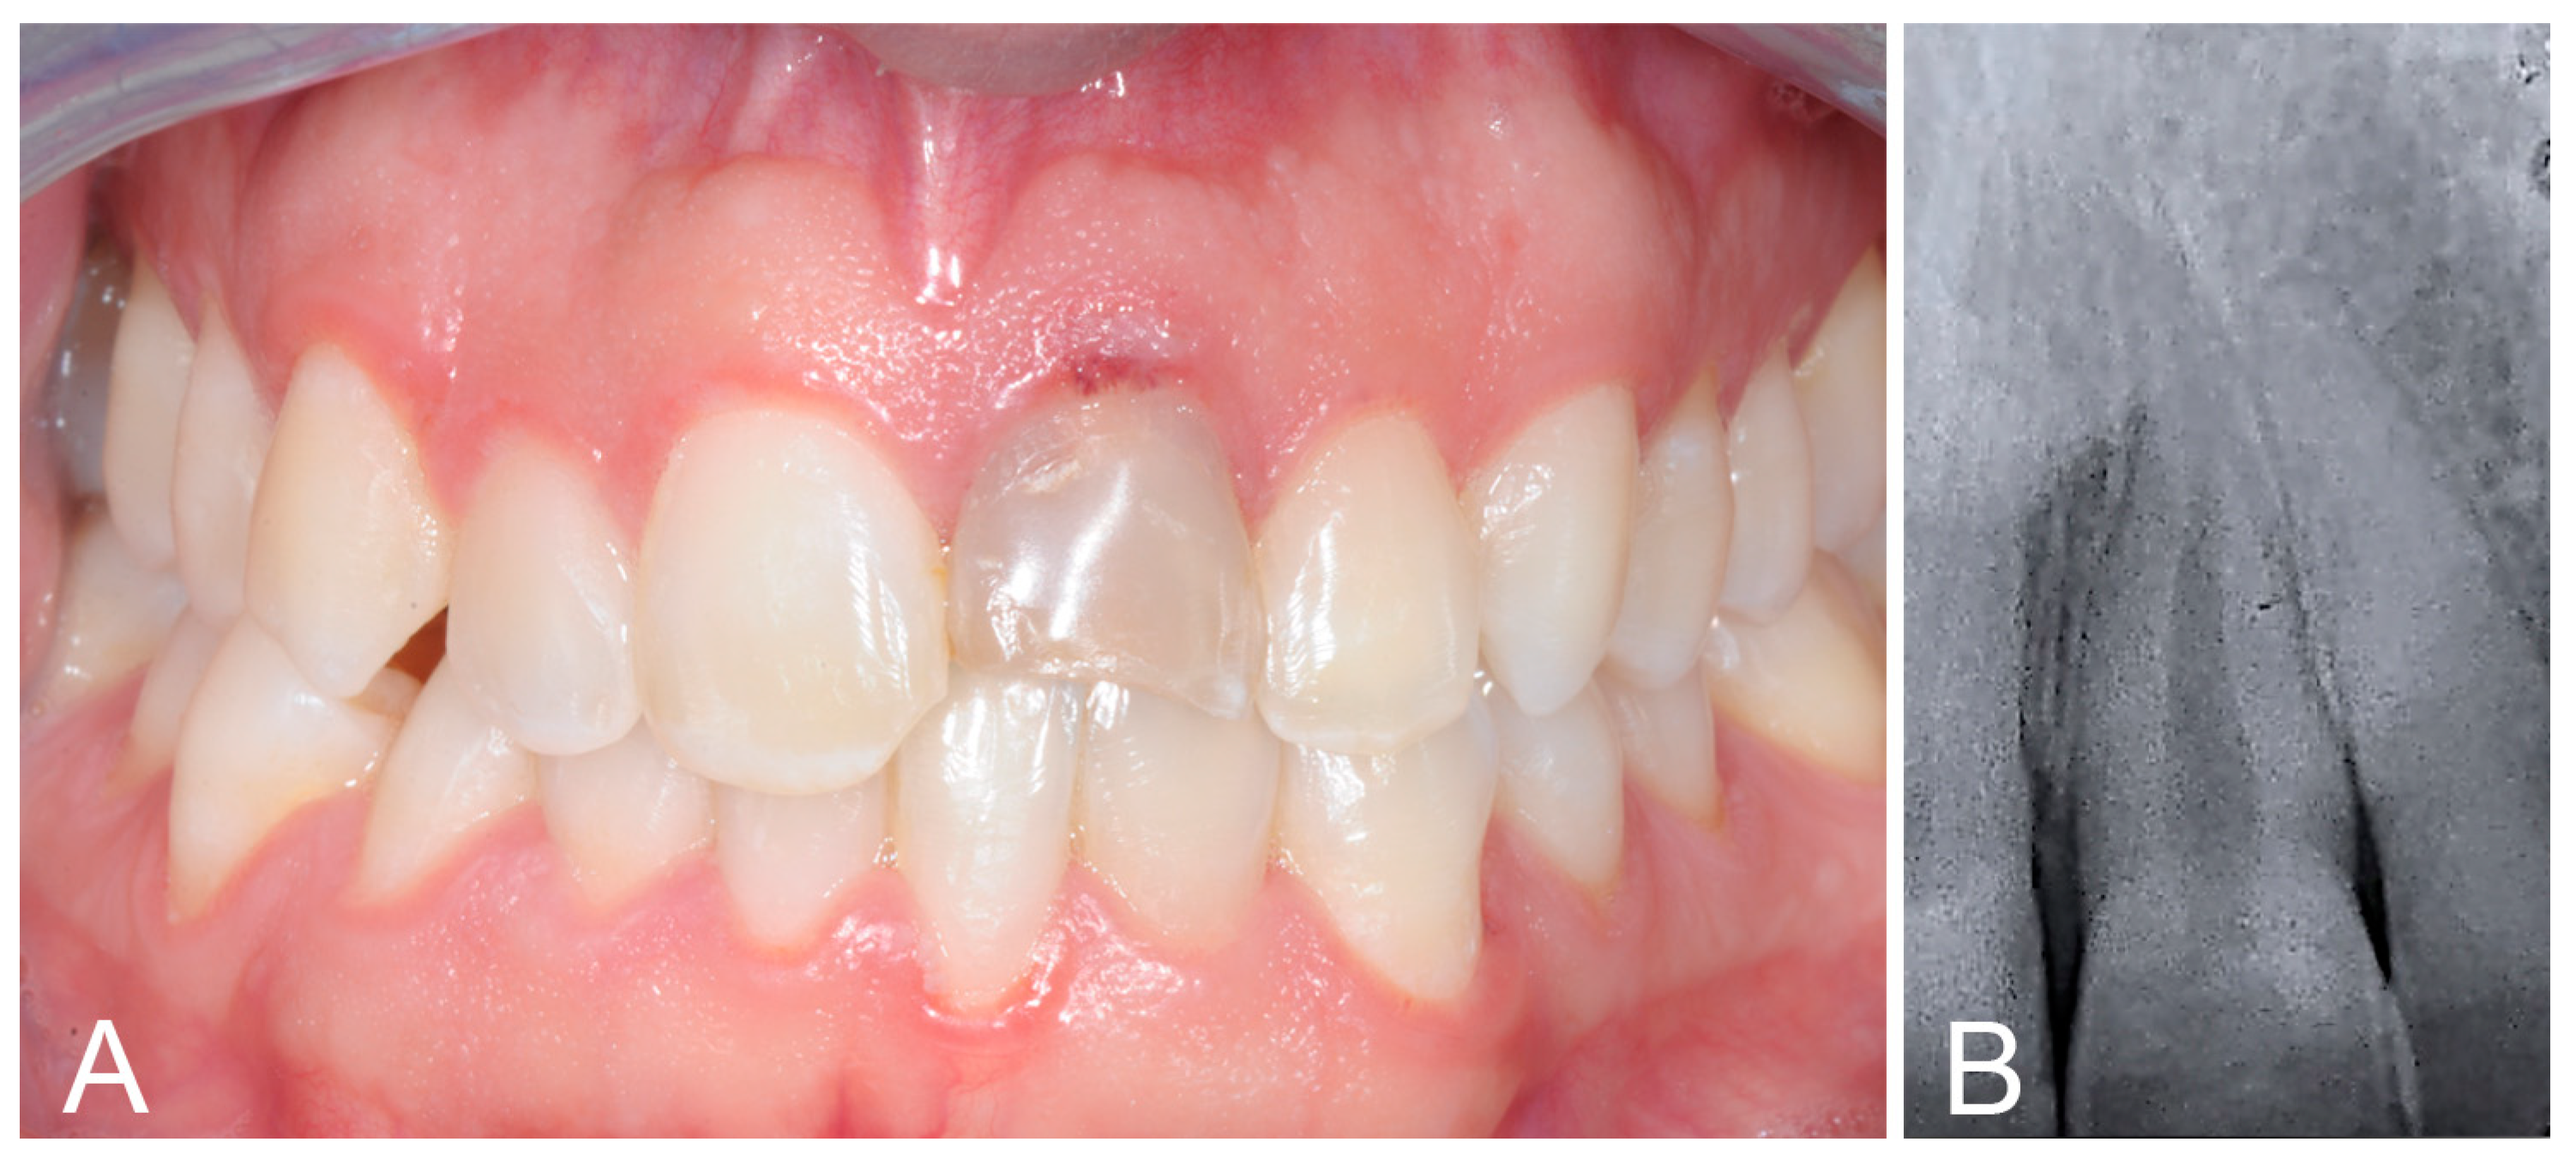

2. Case Report